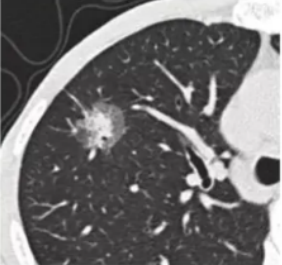

肺结节的密度根据其是否掩盖其中走形的血管和支气管分为实性结节、纯磨玻璃结节、混合磨玻璃结节(指其内既有纯磨玻璃密度、又有实性部分)。下面通过图片来展示。

纯磨玻璃结节

混合磨玻璃结节